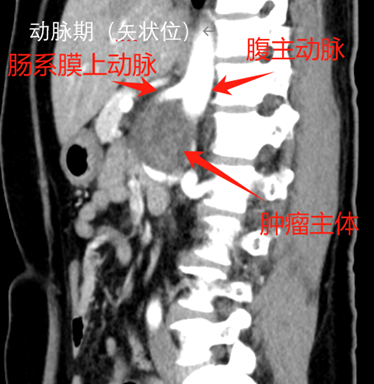

l CT:腹膜后偏左囊实性团块,边界清,增强实性部分不均匀轻中度强化,5.3*7.8*5.9cm,临近组织受推压。

7. 分离顺序:上极→内侧→下极→外侧→向中心。肿瘤上极见多支穿支血管进入肿瘤,其中包括一支粗大血管进入肾脏,复习术前影像,考虑可能为挤压变形的肾动脉,遂保留。

a) 术前细致的影像学评估,判断累及的器官及大血管走向,做到胸中有数。本例虽为神经鞘瘤,增强CT强化不明显 ,但较大肿瘤压迫导致回流不佳形成较多侧支循环,分离时应轻柔精细操作,及时电凝、夹闭或缝扎血管减少出血。肿瘤占位作用也导致正常血管移位(例如上极的肾动脉、肿瘤前上方的肠系膜上动脉),需严格保护。术前需反复阅片。